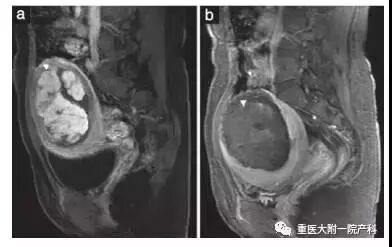

MRI下胎盘植入HIFU治疗前后对比图